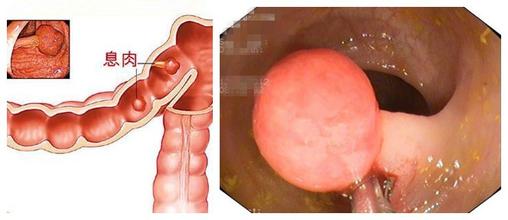

肠息肉是肠道内的病变,它可小至芝麻、绿豆,也可大至核桃。数量可从一个至数百上千个不等。近期几年,肠息肉病的发病率却是日渐高发,且恶变的几率也在不断的增大!但是大多数患者对于肠息肉却不提起警惕,认为肠息肉只是小病。

息肉体积虽小,但危害很大

1、易癌变:许多单发性息肉患者(息肉数量为1),初期不重视,很有可能向多发性息肉转变(息肉数量为多个),而息肉的数量越多,癌变的几率是越高的。

2、肠套叠:有时较大息肉还可以引起肠套叠,以至造成肠梗阻而出现腹痛。

3、脱垂:息肉较大或数量较多时,由于重力的关系牵拉肠粘膜,使其逐渐与肌层分离而向下脱垂。病人排便动作牵拉及肠蠕动刺激,可使蒂基周围的粘膜层松弛,可并发直肠脱垂。